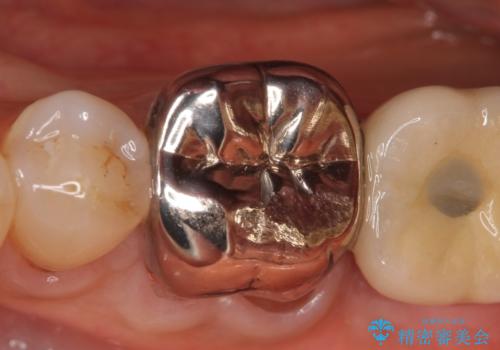

- 左下の奥歯で咬むと痛むので診て欲しいといらっしゃった方の症例です。

検査の結果、左下6番目の歯は神経が死んでおり根尖に病変が出来ていたため、根管治療を行いました。

その後症状の消失を確認後、オールセラミッククラウンによる補綴を行いました。